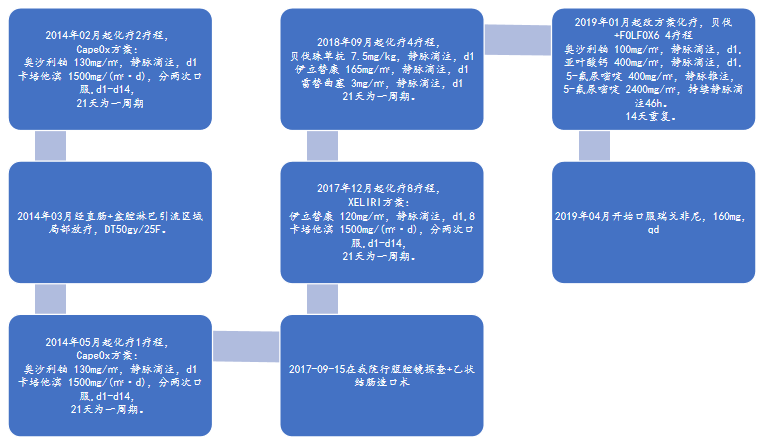

2014年02月起化疗2疗程,

CapeOx方案:

奥沙利铂 130mg/㎡,静脉滴注,d1

卡培他滨 1500mg/(㎡·d),分两次口服,d1-d14,

21天为一周期。

2014年03月经直肠+盆腔淋巴引流区域局部放疗,DT50gy/25F。

2014年05月起化疗1疗程,

CapeOx方案:

奥沙利铂 130mg/㎡,静脉滴注,d1

卡培他滨 1500mg/(㎡·d),分两次口服,d1-d14,

21天为一周期。

2017-09-15在我院行腹腔镜探查+乙状结肠造口术。

2017年12月起化疗8疗程,

XELIRI方案:

伊立替康 120mg/㎡,静脉滴注,d1,8

卡培他滨 1500mg/(㎡·d),分两次口服,d1-d14,

21天为一周期。

2018年09月起化疗4疗程,

贝伐珠单抗 7.5mg/kg,静脉滴注,d1

伊立替康 165mg/㎡,静脉滴注,d1

雷替曲塞 3mg/㎡,静脉滴注,d1

21天为一周期。

2019年01月起改方案化疗,贝伐+FOLFOX6 4疗程

奥沙利铂 100mg/㎡,静脉滴注,d1,

亚叶酸钙 400mg/㎡,静脉滴注,d1,

5-氟尿嘧啶 400mg/㎡,静脉推注,

5-氟尿嘧啶 2400mg/㎡,持续静脉滴注46h。

14天重复。

2019年04月开始口服瑞戈非尼,160mg,qd